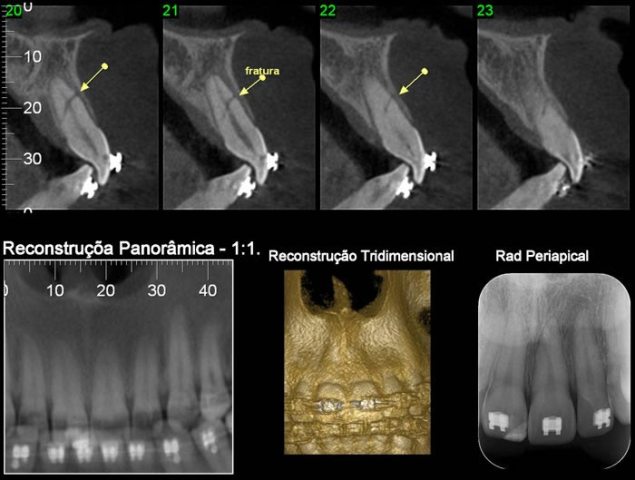

CASO 3 - Fratura de ATM

Paciente com história clínica de trauma. Fratura no côndilo direito com deslocamento do fragmento para medial e deslogamento do côndilo para lateral da cavidade articular.